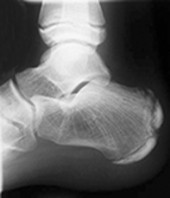

A 13-year-old soccer player presents with a four-week history of aching anterior right knee pain that lasts about 24 hours following training and matches. There is no history of direct trauma, but he has experienced a significant growth spurt during the last six months. Clinical examination reveals swelling and tenderness over the tibial tuberosity, absence of a knee joint effusion, stable knee ligaments and no patellofemoral irritability. X-ray shows a normal tibial tuberosity, with overlying soft tissue swelling.